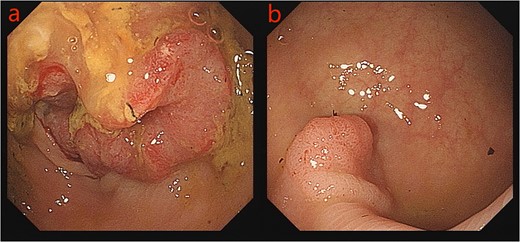

Given the patient’s unsuitability for immediate radical surgical resection, the patient was administered monotherapy with capecitabine to control tumor progression. During an outpatient follow-up, a slight enlargement of the tumor was observed in the ascending colon region. To further understand the patient’s condition, he was readmitted to the hospital, to undergo laboratory tests, serum CEA: 26.10 ng/ml, uric acid: 447 umol/L, and platelet levels were normal. Repeated enhanced CT scanning of the abdomen revealed complete recovery from the obstruction (Fig. 3). To ascertain the nature of the ascending colon tumor,a repeat colonoscopy examination through colostomy showed the sigmoid and ascending colon tumor. The biopsy of the ascending colon tumor revealed an adenocarcinoma (Fig. 4). Given the patient’s concomitant small B-cell lymphoma and primary thrombocytopenia, surgical treatment was decided after a multi-disciplinary team discussion.

Colonoscopy images: a: sigmoid tumor; b: ascending colon tumor.